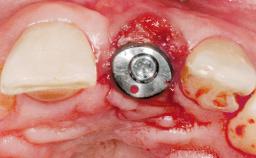

Immediate Flapless Placement of an Implant in a Maxillary Left Central Incisor Site

A 42-year-old female patient was referred to our clinic at the School of Dentistry of the University of São Paulo in November 2004, presenting a deficient restoration in the upper left central incisor. The clinical examination revealed no gingival retraction or any signs of gingival inflammation and, therefore, previous periodontal treatment was not considered. The patient presented a high lip line at full smile and a thin tissue biotype. This combination characterized a high-risk situation from an anatomic point of view, which required careful preoperative planning and cautious surgical execution.

Placement Protocol Immediate implant placement

Tooth Site Maxillary incisor or canine

Socket Morphology Single-root socket

Socket Integrity Sufficient, with intact bone walls